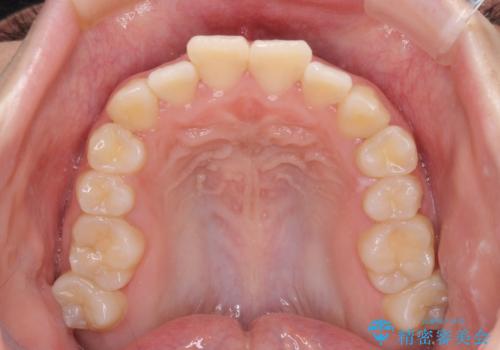

上下非接触で突出した前歯 ワイヤー装置による抜歯矯正

- 上下前歯の隙間と口元の出っ張った感じを気にして来院された患者様です。

上下の隙間は舌突出癖によるもので、またその癖により前歯が前方に出ている状態でした。

口元の出っ張りを改善するため、上下左右第一小臼歯4本を抜去し、ワイヤー装置にて矯正治療を行うこととしました。

舌の突出癖を改善するためのトレーニングをしっかりと行っていただいたことで、比較的スムーズに治療を進めることができました。

口元の突出感もしっかりと改善することができました。